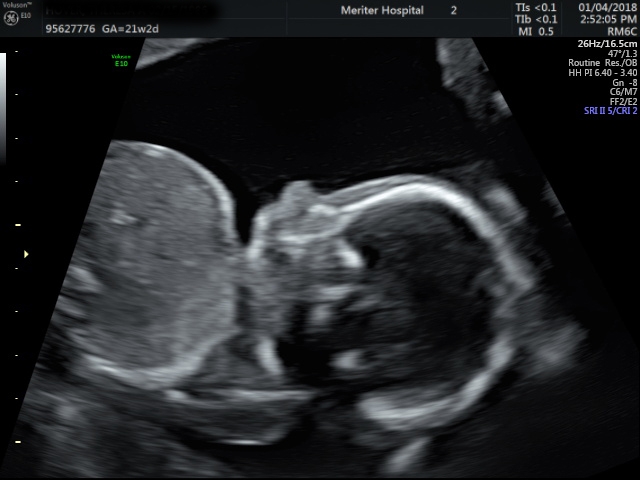

I'm 21 weeks (EDD May 15th) and we have our anatomy scan TODAY!

• @ReesaAnne16 woohoo congrats!!! Love the US!! I'm really hoping I will be getting a 3D US soon!!! Soooo cute!! So thrilled for you!

@ReesaAnne16 yay! So exciting. I love seeing from pictures. Congrats! Can’t wait for some new ones in 2 weeks. Such a long wait.

• @ReesaAnne16 Love the pics!! So adorable :)